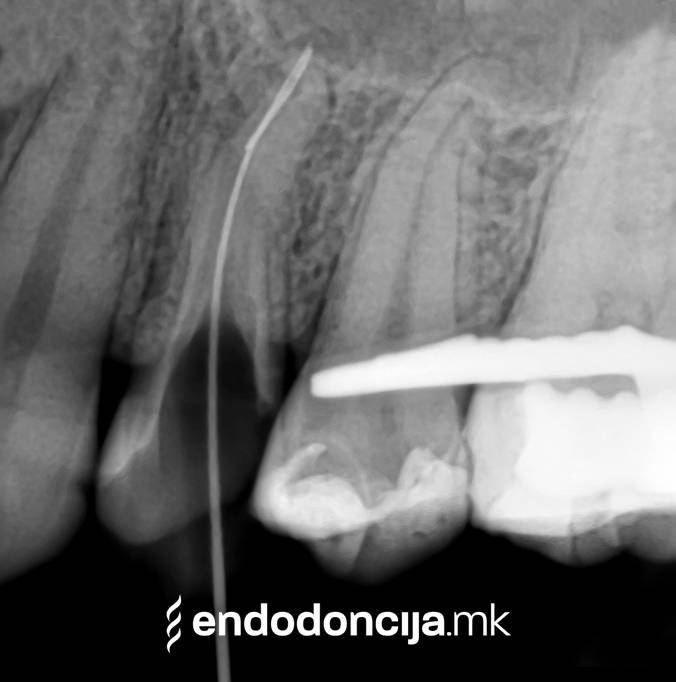

Εκτός από την ανίχνευση των ριζικών καναλιών, η ενδελεχής προετοιμασία και η απολύμανση του ριζικού σωλήνα είναι η προϋπόθεση για μια επιτυχημένη συνολική θεραπεία. Μέσω της χρήσης των νεότερων οργάνων και αντιβακτηριακών διαλυμάτων, όλα τα υπολείμματα ιστών και τα βακτήρια που υπάρχουν μπορούν να εξαλειφθούν.

Με τη σωστή θεραπεία, όχι μόνο οι οξείες φλεγμονές αλλά και οι χρόνιες μπορούν επίσης να αντιμετωπιστούν με επιτυχία. Αυτά μπορεί να προκαλέσουν πόνο ή μερικές φορές ακόμη και εντελώς χωρίς συμπτώματα. Η έγκαιρη ανίχνευση και εξάλειψη τέτοιων φλεγμονών είναι ζωτικής σημασίας για τη μακροχρόνια συντήρηση των δοντιών.